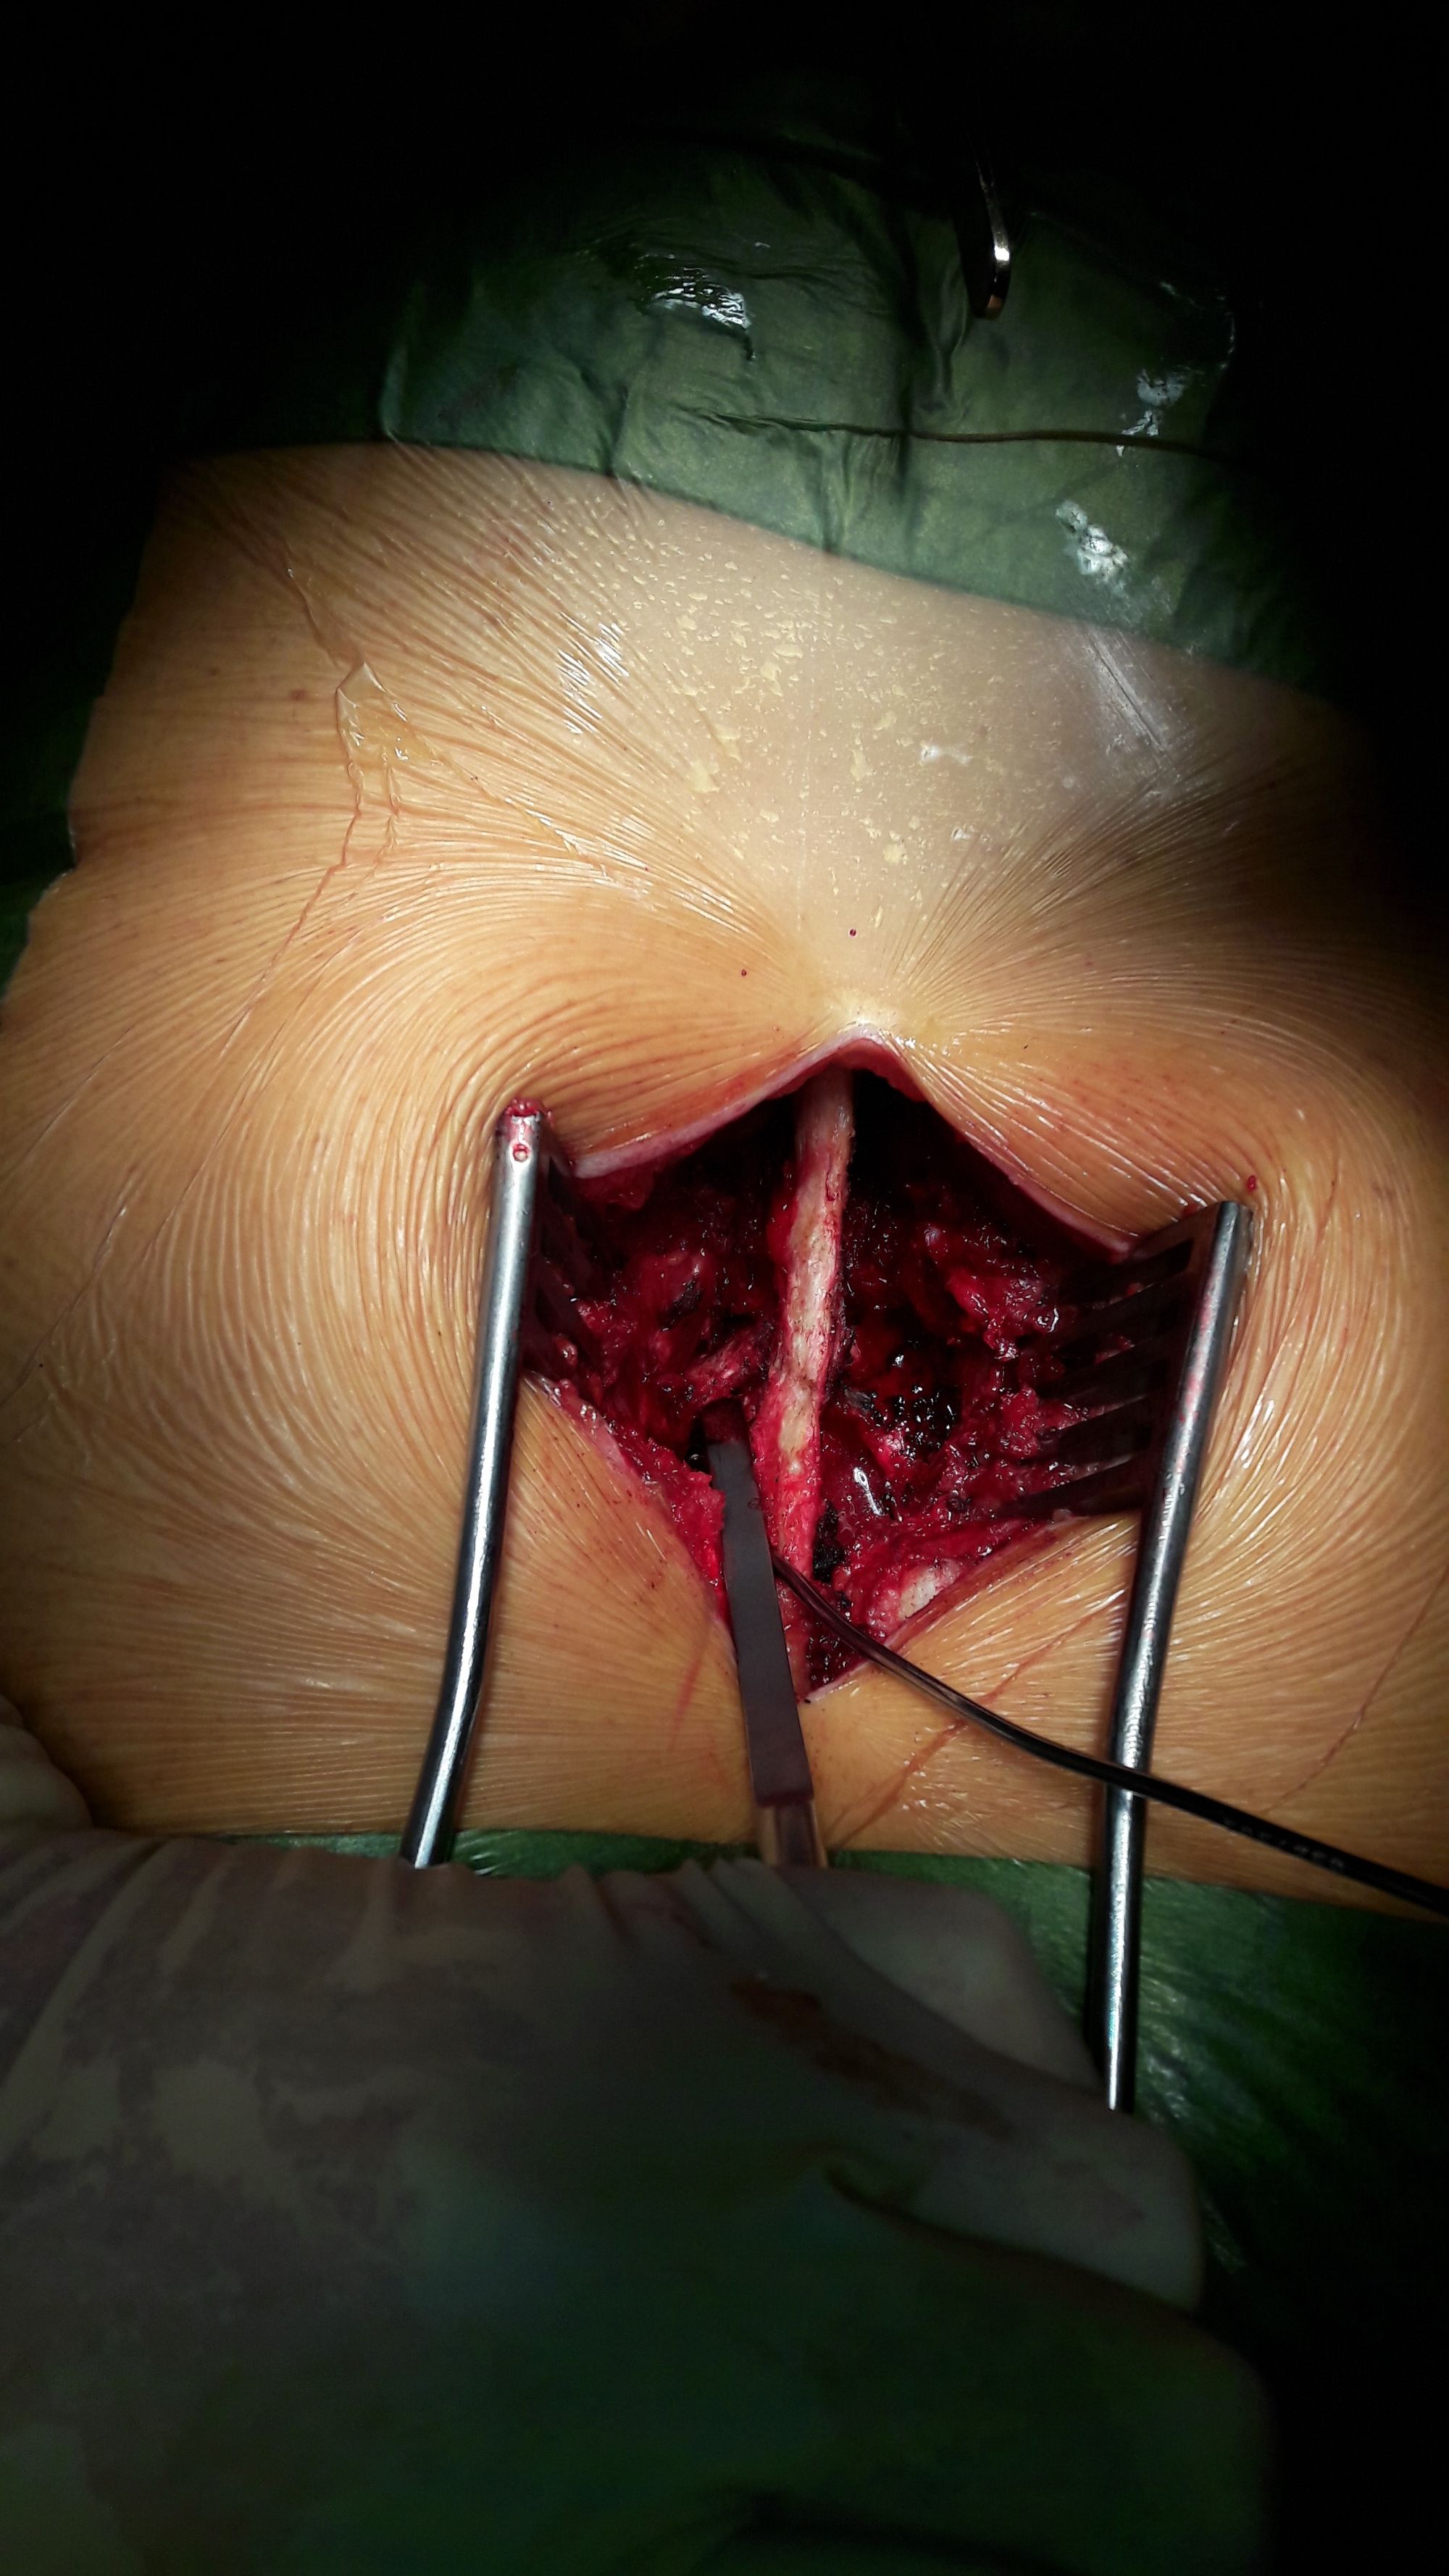

The patient is placed in prone position on a Hall frame. A medial sagittal incision is made over the spinous processes at the level of the spinal stenosis. The erector spinae muscles are detached from both sides of the spinous processes and laminae, down to the facet joints laterally which are disengaged (Fig. 2).

The inferior quarter of the inferior facet joint processes subjacent to the compressed level is resected using an osteotome using a strictly transverse osteotomy cut (Fig. 3).

The lumbar canal is recalibrated using a technique similar to the one described by Sénégas [9], with a cephalic hemilaminectomy of the inferior vertebra, and a medial facetectomy using a 4 or 5mm Kerrison rongeur. The bone cut extends directly above the pedicle to allow unroofing of the recess. Downwards and outwards, the resection must be completed to allow the hook to pass freely into the foramen without damaging the nerve root. Upwards and outwards, the cut extends directly above the inferior edge of the lamina of the superior vertebra.